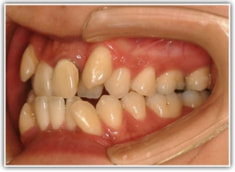

治療開始から約1年後

骨格的な下顎前突の傾向は強くはありませんが、歯牙の状態によって反対咬合が認められます。LowTongue(低位舌)もあります。

修復歯、補綴歯もあります。下顎8番が水平埋伏しています。